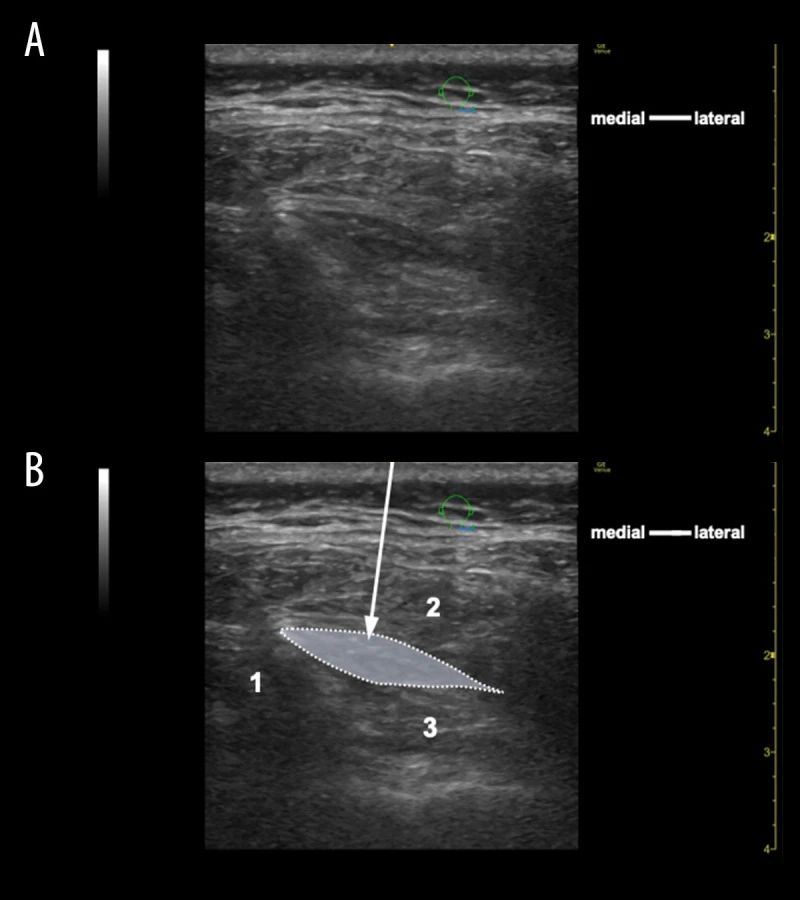

隨后,在超聲引導(dǎo)下,用5 mL 0.75%羅哌卡因?qū)τ覀?cè)半棘頭肌和頭斜肌下肌之間的束間間隙進(jìn)行水分離,從而立即完全緩解了右側(cè)枕大神經(jīng)支配區(qū)域的頭痛(圖1)。

圖1. 超聲影像顯示右側(cè)半棘肌和下斜頭肌之間的位置及水解剝離過程。(A, B) 在水解剝離過程中(超聲出平面技術(shù))。箭頭指示針頭的位置。虛線表示注射溶液的范圍。(1) C2棘突;(2) 半棘肌;(3) 下斜頭肌。